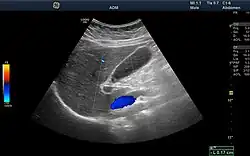

Ultrasound

Medical ultrasound uses high frequency broadband sound waves in the megahertz range that are reflected by tissue to varying degrees to produce (up to 3D) images. This is commonly associated with imaging the fetus in pregnant women. Uses of ultrasound are much broader, however. Other important uses include imaging the abdominal organs, heart, breast, muscles, tendons, arteries and veins. While it may provide less anatomical detail than techniques such as CT or MRI, it has several advantages which make it ideal in numerous situations, in particular that it studies the function of moving structures in real-time, emits no ionizing radiation, and contains speckle that can be used in elastography. Ultrasound is also used as a popular research tool for capturing raw data, that can be made available through an ultrasound research interface, for the purpose of tissue characterization and implementation of new image processing techniques. The concepts of ultrasound differ from other medical imaging modalities in the fact that it is operated by the transmission and receipt of sound waves. The high frequency sound waves are sent into the tissue and depending on the composition of the different tissues; the signal will be attenuated and returned at separate intervals. A path of reflected sound waves in a multilayered structure can be defined by an input acoustic impedance (ultrasound sound wave) and the Reflection and transmission coefficients of the relative structures.[19] It is very safe to use and does not appear to cause any adverse effects. It is also relatively inexpensive and quick to perform. Ultrasound scanners can be taken to critically ill patients in intensive care units, avoiding the danger caused while moving the patient to the radiology department. The real-time moving image obtained can be used to guide drainage and biopsy procedures. Doppler capabilities on modern scanners allow the blood flow in arteries and veins to be assessed.